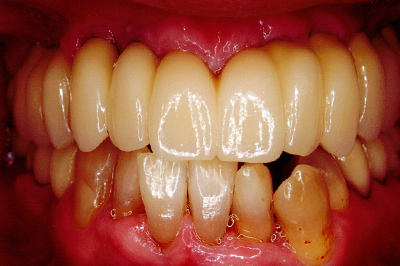

治療例2

歯ぐきが安定した状態

土台をたてた

噛める機能を回復

| ご費用 | 手術費用人工歯根 1本275,000円(税込) 上部構造 88,000円~110,000円(税込) |

|---|---|

| リスク・副作用 | 保険非適応(自費診療) 特定の全身疾患や持病のある方、顎骨密度の足りない方、妊娠中の方は手術ができない場合があります。 下顎のインプラント手術の際、偶発症のリスクがあります。 人工歯根が顎骨と癒着しないリスクがあります。 インプラント周囲炎になるリスクがあります。 |